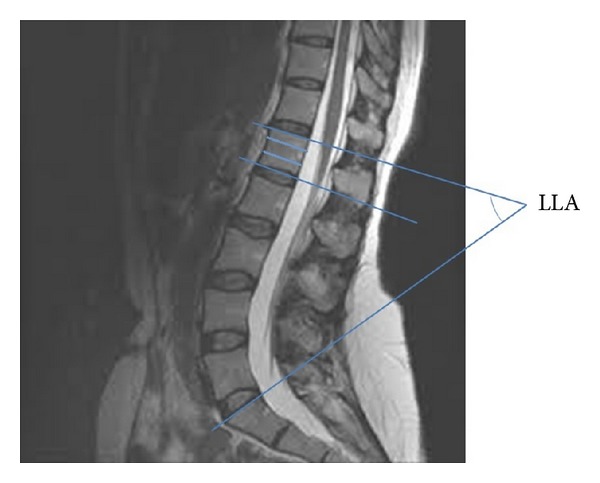

髓圆锥(CM)和鞘囊(TS)终止的水平是不同的。在这项研究中,我们试图通过MRI扫描将这些变化与腰椎前凸角(LLA)联系起来。回顾性研究使用可用的腰椎MRI扫描。CM终止水平(CMLT)和TS终止水平(TSLT)根据椎体水平分为3部分后进行识别。还为每个人确定了LLA。线性回归模型拟合了141个人的可用数据。其中70人为男性,71人为女性。CMLT最常见的位置是L1的上三分之一(32.6%),TSLT最常见的位置是S2的中三分之一(29.8%)。平均LLA为46°(20°-81°)。CMLT最近端位于T12的上三分之一,而最远端位于L2的上三分之一。最近端的TSLT位于S1的上三分之一,而最远端的TSLT位于S3-S4椎间盘间隙。CMLT与LLA呈正相关。综上所述,CMLT和TSLT可能与LLA的变化有关。

The level of termination of the conus medullaris (CM) and thecal sac (TS) is subject to variations. We try to correlate in this study these variations with the lumbar lordosis angle (LLA) using MRI scans. A retrospective study was conducted using available MRI scans of the lumbar spine. The CM level of termination (CMLT) and the TS level of termination (TSLT) were identified according to a vertebral level after dividing it into 3 parts. The LLA was also identified for each individual. Linear regression models were fitted to the data available on 141 individuals. Of these 70 were males and 71 were females. The most common site of CMLT was at the upper third of L1 (32.6%) and that of the TSLT was at the middle third of S2 (29.8%). The mean LLA was 46° (20°-81°). The most proximal CMLT was at the upper third of T12, whereas the most distal one was at the upper third of L2. The most proximal TSLT was at the upper third of S1, whereas the most distal one was at S3-S4 disc space. The CMLT showed a positive correlation with the LLA. In conclusion the CMLT and TSLT may be related to variations of the LLA.